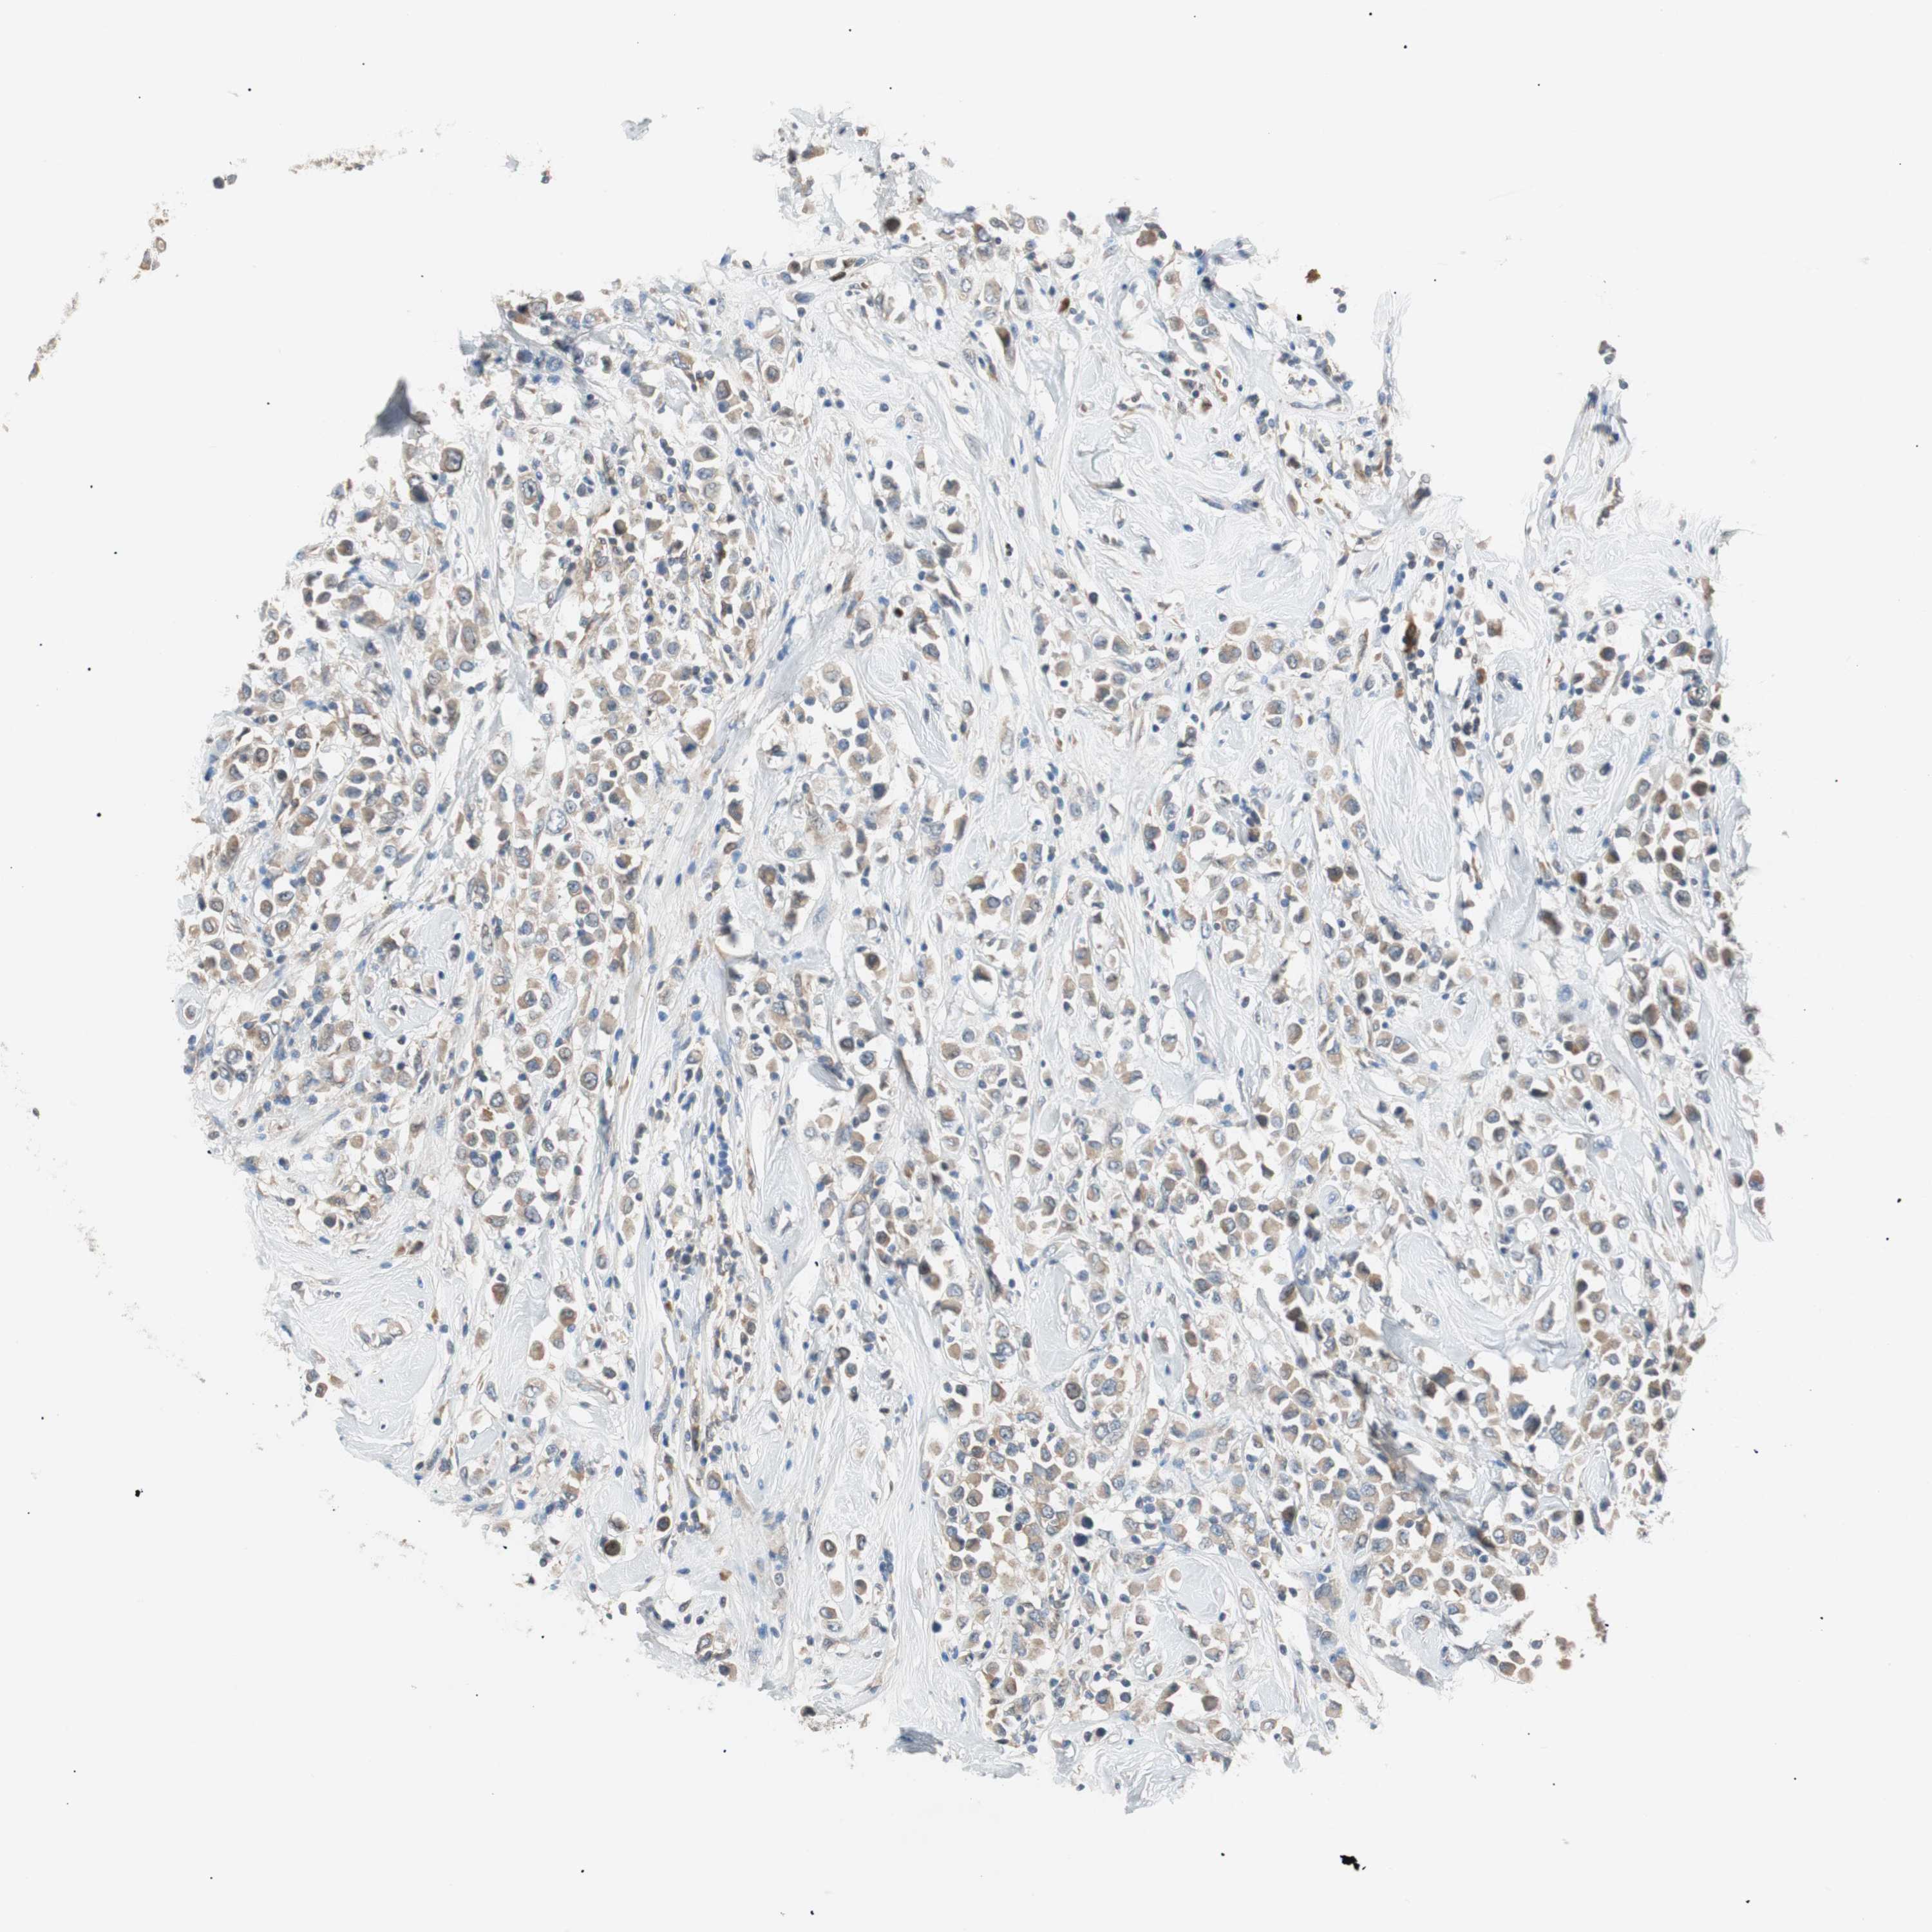

CANCER BREAST CANCER Show tissue menu

BRCA TCGA BRCA VALIDATION PROTEIN EXPRESSION